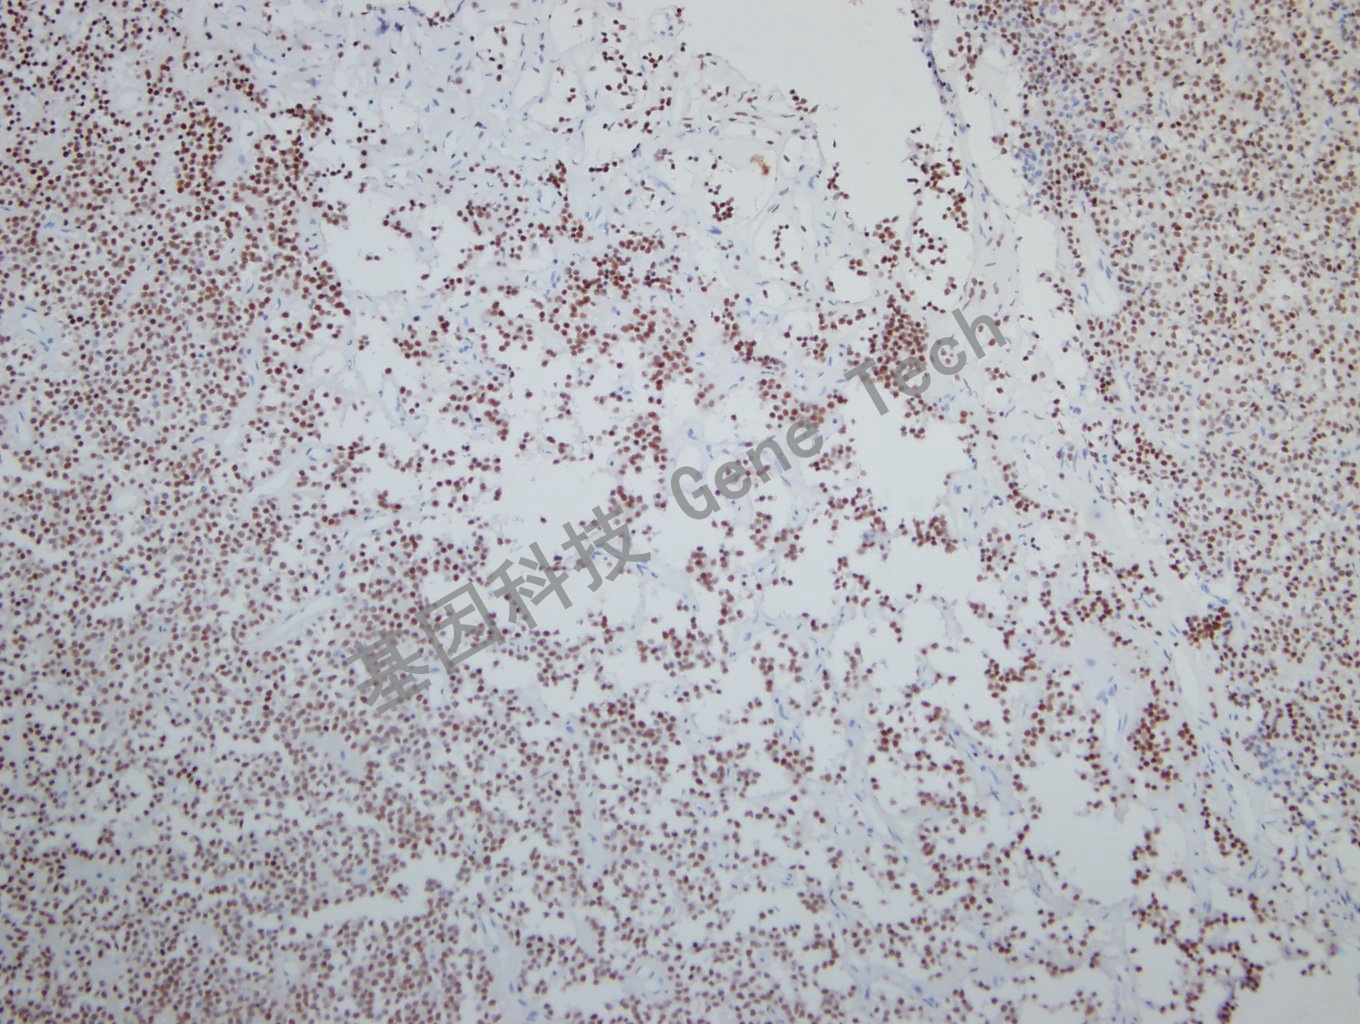

垂体腺瘤石蜡切片,用 SF-1(GT2317)染色,细胞核阳性,DAB显色。